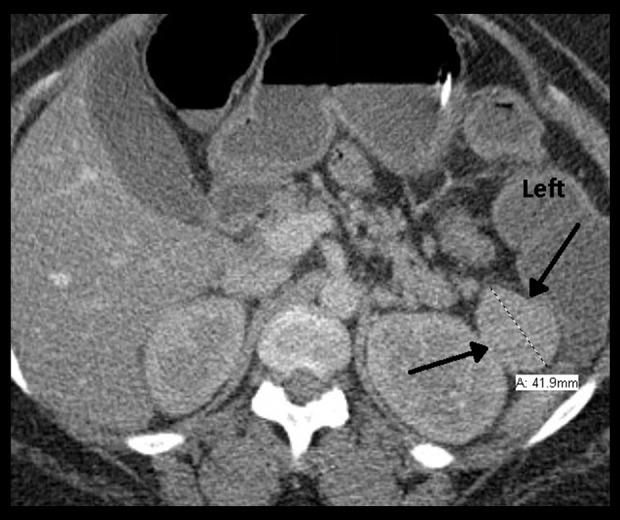

BACKGROUND VIPomas are rare neuroendocrine tumors typically located in the pancreas. The majority of cases autonomously secret vasoactive intestinal polypeptide (VIP), which can result in profuse, refractory, watery diarrhea. The fluid and electrolyte imbalance can progress to dehydration and profound hypokalemia, resulting in the watery diarrhea, hypokalemia, achlorhydria (WDHA) syndrome. One previous case of a pancreatic VIPoma progressing to hypokalemic rhabdomyolysis has been described. CASE REPORT A 33-year-old woman presented with 3 months of progressive, refractory diarrhea and weakness. Her serum VIP level was elevated and imaging discovered a mass in the region of the pancreatic tail. Laparoscopic partial pancreatic resection was performed and a 3.7-cm diameter, solitary stage T2 N0 M0, well-differentiated carcinoma was removed. CONCLUSIONS A high index of suspicion is important when diagnosing chronic diarrhea. Minimally invasive surgery is an option in the surgical treatment of pancreatic VIPoma.

背景 血管活性肠肽瘤(VIPoma)是一种罕见的神经内分泌肿瘤,通常位于胰腺。大多数病例会自主分泌血管活性肠肽(VIP),这可导致大量、难治性水样腹泻。体液和电解质失衡可发展为脱水和严重低钾血症,导致水样腹泻、低钾血症、无胃酸(WDHA)综合征。此前曾有一例胰腺VIPoma进展为低钾性横纹肌溶解症的病例报道。病例报告 一名33岁女性出现3个月的进行性、难治性腹泻和乏力。她的血清VIP水平升高,影像学检查发现胰尾区域有一个肿块。进行了腹腔镜胰腺部分切除术,切除了一个直径3.7厘米、孤立的T2 N0 M0期、高分化癌。结论 在诊断慢性腹泻时,高度的怀疑指数很重要。微创手术是胰腺VIPoma手术治疗的一种选择。